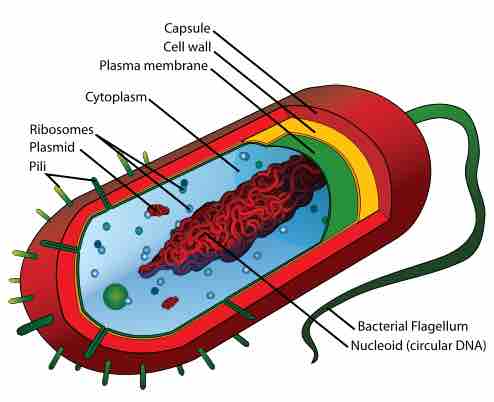

β-Lactam (beta-lactam) and glycopeptide antibiotics work by inhibiting or interfering with cell wall synthesis of the target bacteria.

Several types of antimicrobial drugs function by disrupting or injuring the plasma membrane.